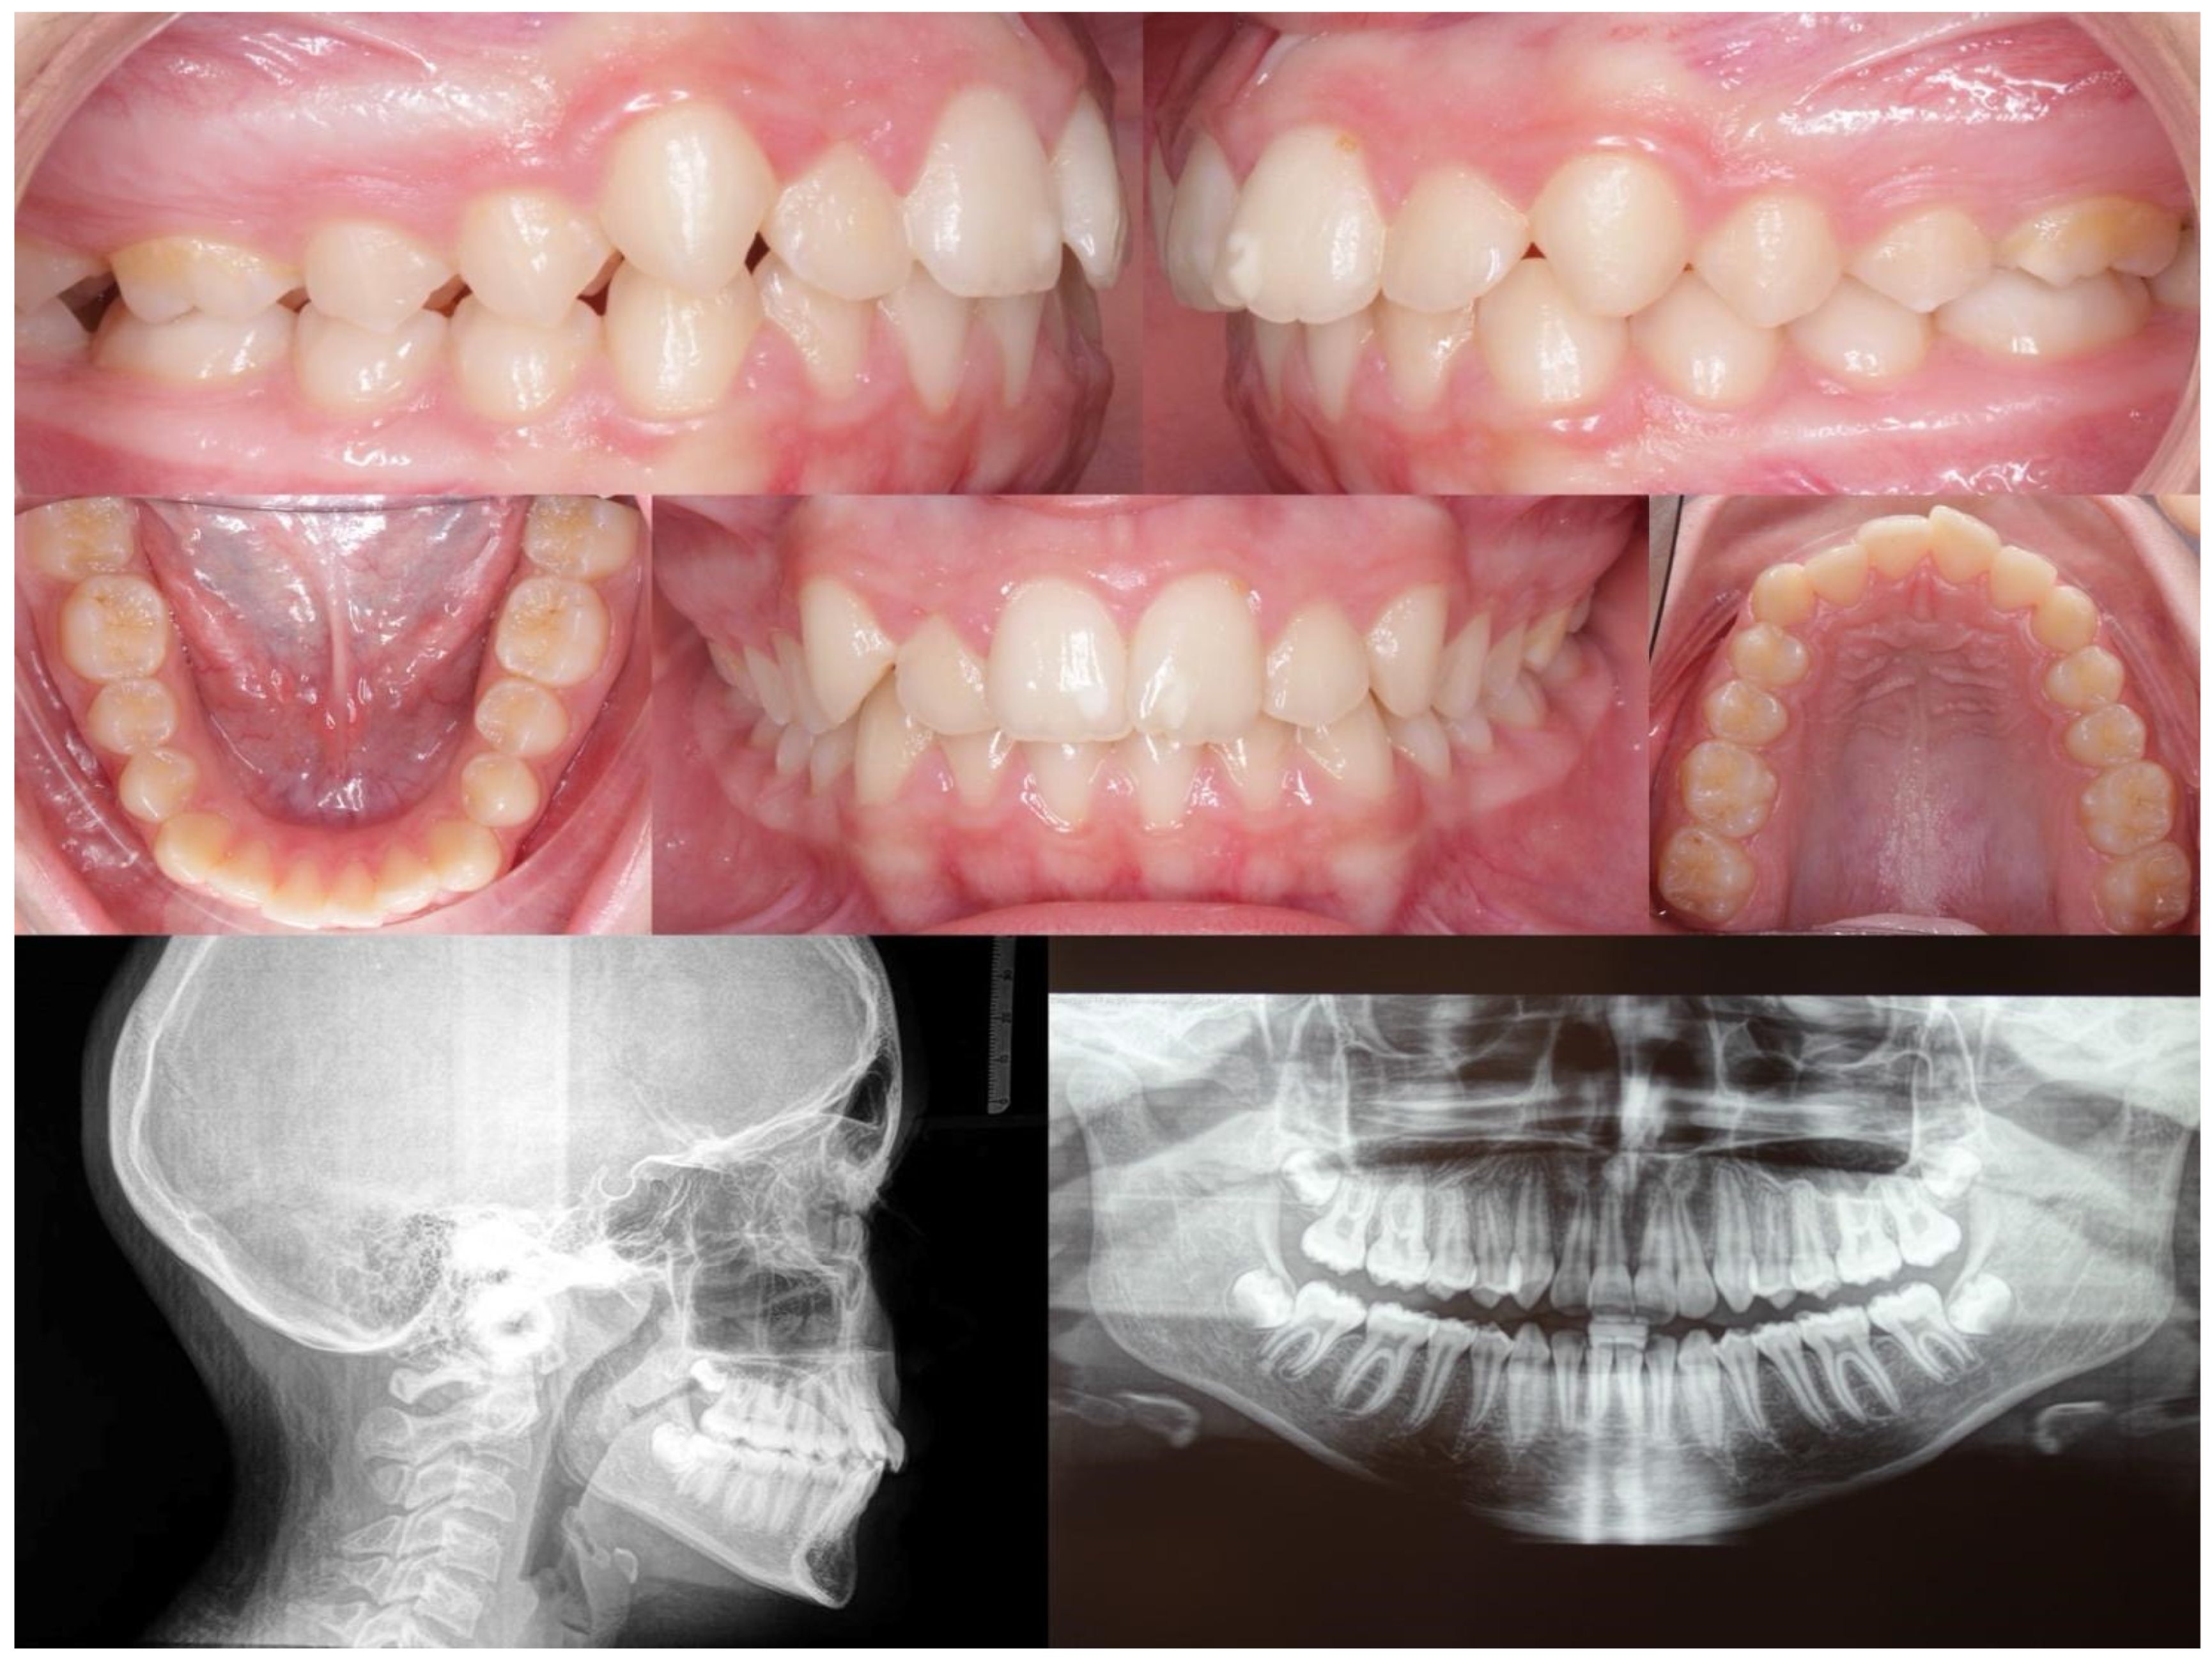

Below, the initial (Figure 2) and final (Figure 3) clinical records of a patient with mandibular deviation, treated with the Group 1 protocol, are presented.

Figure 2.

Initial right, left, front, upper, and lower orthopantomography and lateral cephalometric radiographs.